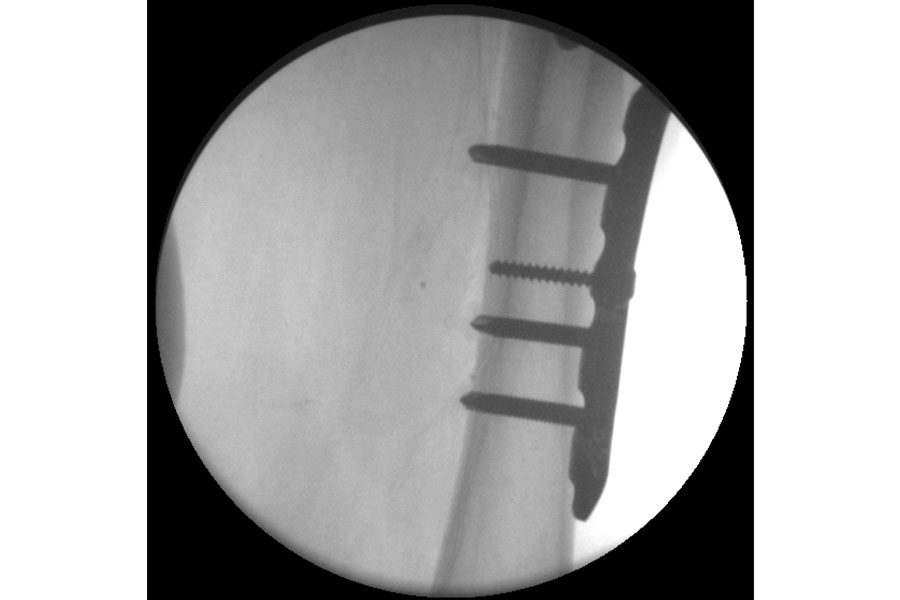

Trauma

Case 1